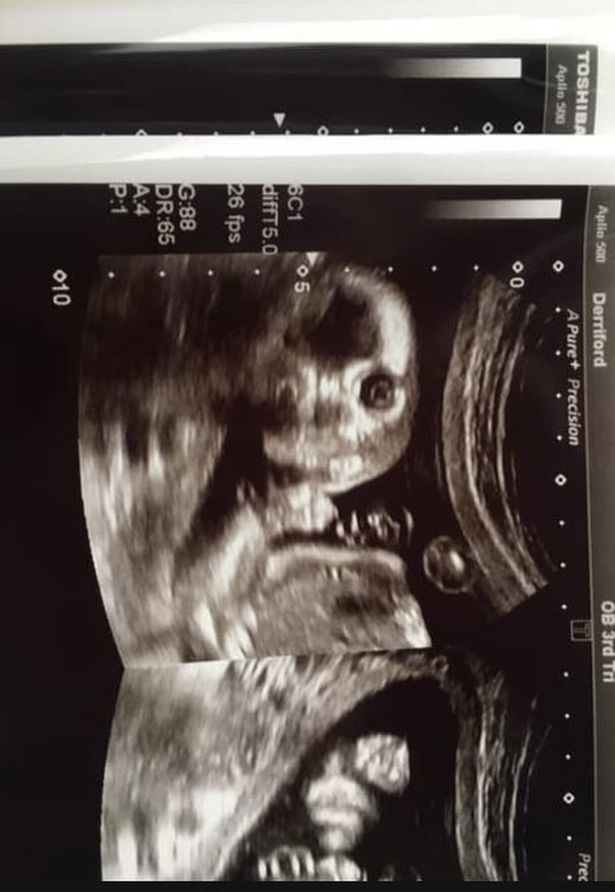

不过做B超时,医生和格里尔都吃了一惊,因为格里尔腹中的小宝宝突然转了一个位置,目光直视镜头,看起来很机灵、别具神采。医生说这样的情形是很罕见的。

做B超时,格里尔42岁的丈夫克林特·琼斯(Clint Jones)也在场,两人起初都觉得有点“恐怖”、有点震惊,但很快,两人都笑了起来。

格里尔将她宝宝的可爱B超照片发布在社交媒体上,配文说,大家都看过许多标准的、可爱的B超扫描照片,但她的宝宝照片有点罕见,非常有趣。

网友们都被宝宝的B超照片逗乐了,有人笑说宝宝好像小鬼,也有网友说宝宝像小机器人,说笑之后,大家都在期待宝宝出生后的样子,祝福准妈妈格里尔。